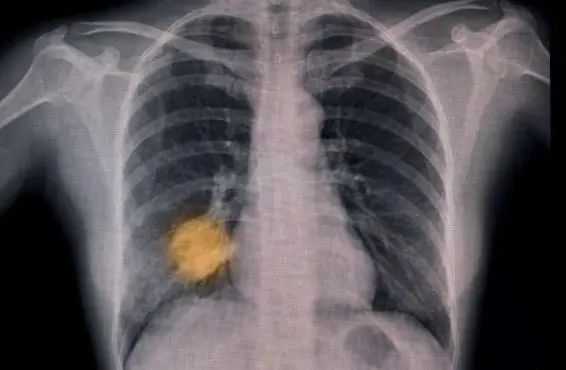

另一項進(jìn)行中的試驗正在追蹤英國6家醫(yī)院的15萬名患者,測試AI能否根據(jù)胸部X光片作出肺癌早期診斷,發(fā)現(xiàn)哪些患者需要當(dāng)天接受計算機斷層掃描(CT)。

人工智能工具的試驗和兩年一次的篩查有望幫助人們更早地發(fā)現(xiàn)肺癌。

圖片來源:《自然·醫(yī)學(xué)》